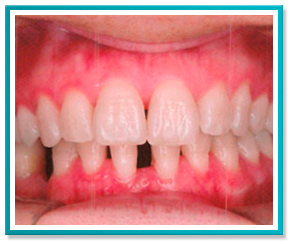

5. PROBLEMAS COM A DENTIÇÃO INFANTIL

Problemas com a dentição de seu filho?

Saiba que quanto antes for a intervenção, mais fácil, rápida e conservadora será a correção.

Veja a seguir as fotos de um caso onde foi necessário trazer para frente o incisivo central que encontrava-se totalmente escondido.

A correção foi feita através de aparelho removível com ação de molas, em menos de 1 ano de tratamento.